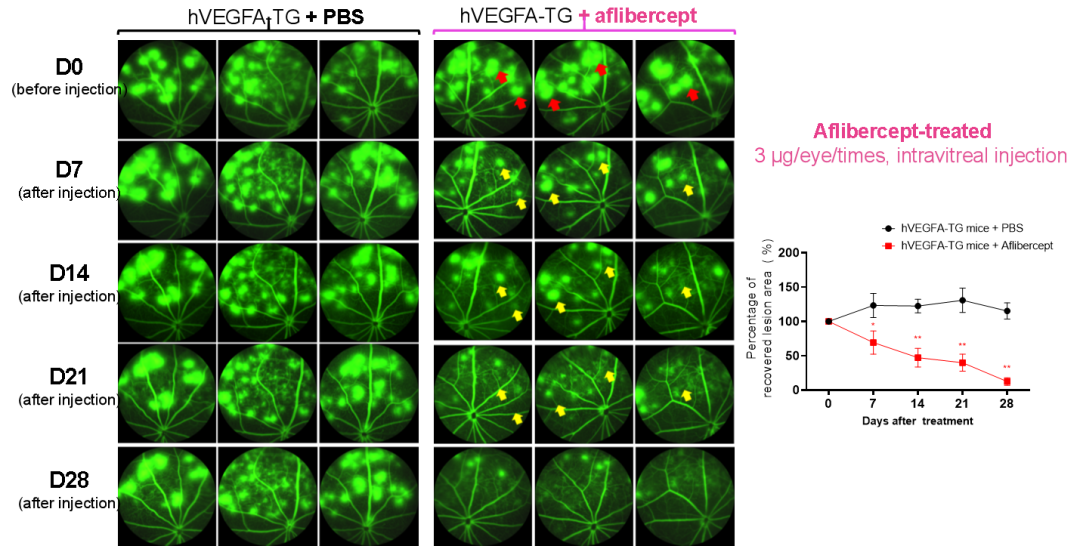

hVEGFA-TG小鼠由视杆细胞特异性启动子驱动人源VEGFA基因CDS序列表达(保留小鼠内源Vegfa基因的表达),该模型自发性出现由VEGFA过表达导致的视网膜和脉络膜血管病变,已助力多个候选药物分子的临床前体内药效评价。

图2 hVEGFA-TG小鼠用于VEGFA靶向药物阿柏西普(Aflibercept)的药效验证